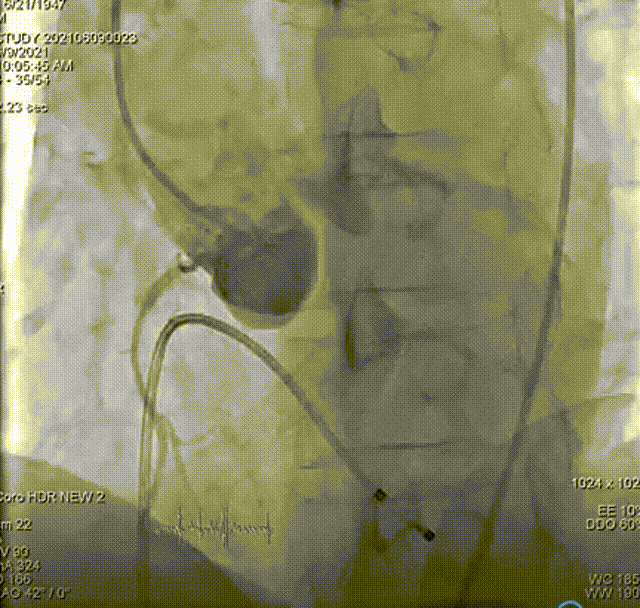

主动脉根部造影,双侧冠脉血流未见明显异常。

选取20mm球囊180bpm频率下快速起搏预扩。球囊扩张后未见反流,左右冠血流未受影响,选择VenusA-Plus 26型号瓣膜植入。

输送系统输送至窦底,行主动脉根部造影,借助无冠窦猪尾造影定位,由于该患者基础心率较缓慢,瓣膜无起搏顺利释放。

术后心电监护未见传导阻滞。即刻造影和测压显示基本无压差和无反流。